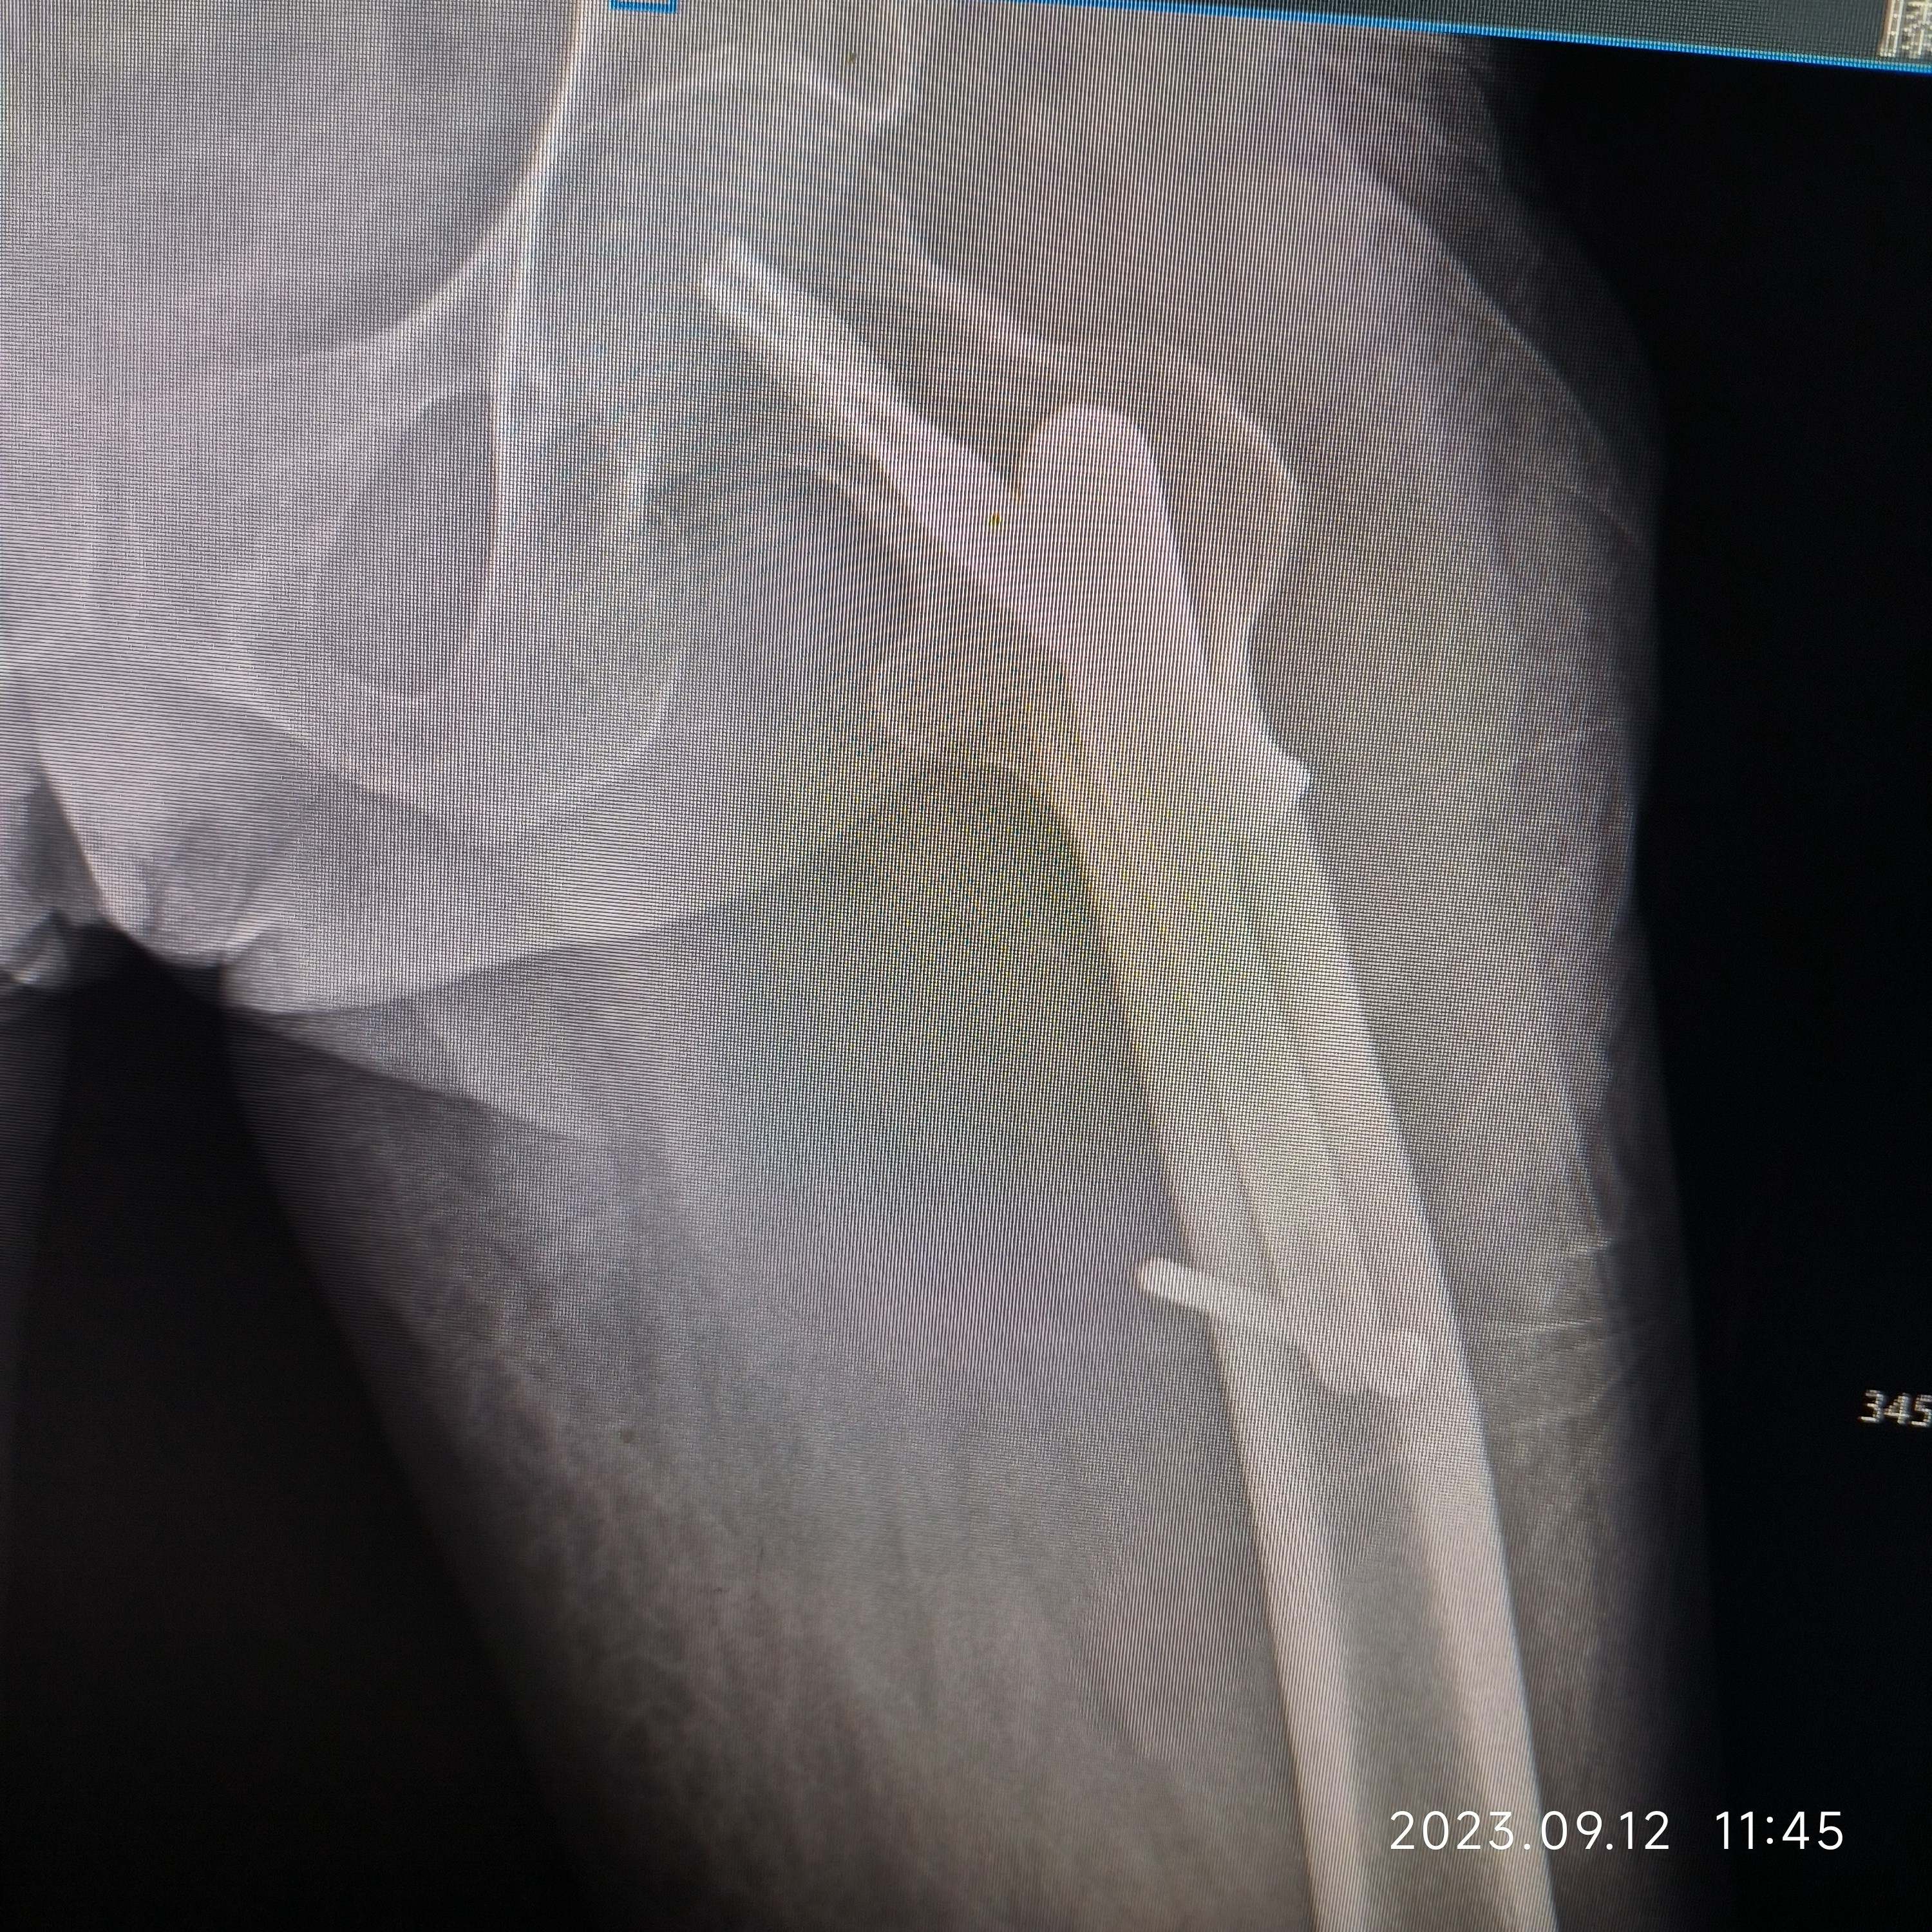

女,80岁,左股骨转子间骨折PFNa。病人营养状况一直不好,胃肠道接受能力非常差,稍微进食油腻基本上一天在10次左右腹泻(常备蒙脱石散、诺氟沙星…),家里老伴身体不好,子女忙都没法在家照顾,强烈要求手术,术前病人血色素6.5g,凝血正常,术中出血700ml左右,低血压报警一次,用了多巴胺后高压维持80mmHg左右,术后输了2U红悬+400ml血浆,第一天复查血色素5.9g,第二天复查血色素6.0g,术后1周复查血色素6.2g……病人精神状态一直还可以……

术后1周晚上,健肢膝关节突然肿胀起来,病人疼痛明显,停抗凝,冷敷后逐渐消下来……